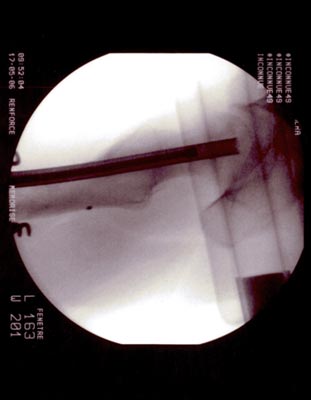

Technique opératoire Le trocart est introduit par voie pertrochantérienne et suit le trajet de la vis. Sa position dans la tête fémorale et dans la nécrose est repérée sous amplificateur de brillance de face et de profil. Une petite pince à séquestre retire les tissus fibreux et nécrosés circonférenciellement après repérage. Un lavage au sérum bétadiné complète le curetage. La moelle osseuse est prélevée (à l'aide du trocart de Mallarmé) sur la crète iliaque selon la technique classique. La moelle recueillie est d'autant plus riche en cellules souches qu'elle a été aspirée par petites fractions (2 ml). Ceci permet de réduire le degré de dilution par le sang périphérique. Elle est ensuite mélangée extemporanément avec le biomatériau. En général : 5 ml pour 5 cc de corail naturel. Sous contrôle Rx., le greffon est introduit à l'aide d'un trocart jusque dans la tête au niveau de la zone curetée : L'appui-contact avec 2 C.B est immédiat. Faut-il mettre en décharge avec traction et combien de temps ? Il ne sera possible de répondre à cette question que lorsque l'on saura avec précision la durée des phases de déminéralisation-reminéralisation du composite biomatériau-moelle osseuse aboutissant à de l'os néo- formé mécaniquement solide. C'est aux fondamentalistes de nous apporter la réponse.

OSTEONECROSE ASEPTIQUE de la H.D. Intervention en mai 2006